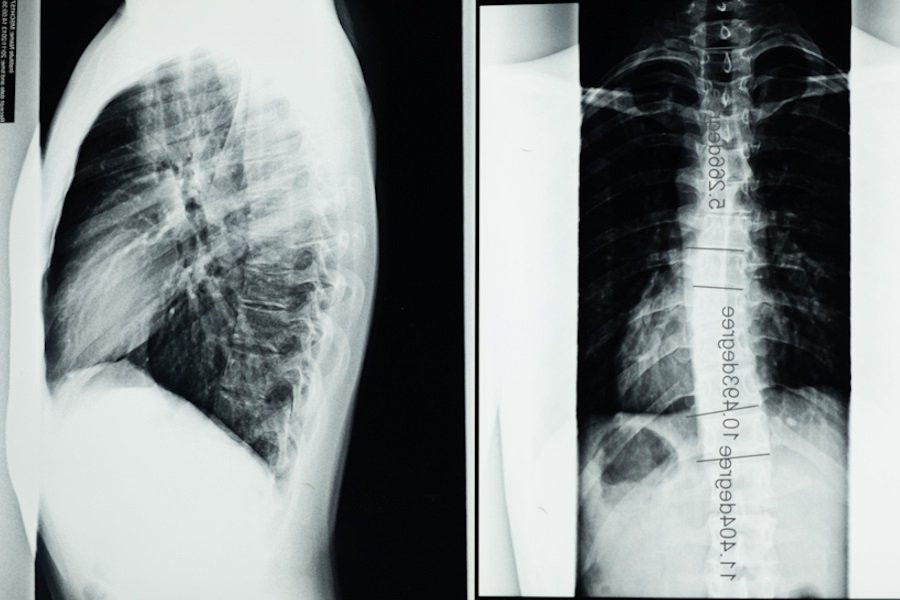

С использованием передовой методики, разработанной в University of California Riverside, ученые достигли прорыва в области медицины, позволяя впервые получать изображения спинного мозга человека с высоким разрешением прямо во время операций.

Методика, известная как функциональная ультразвуковая визуализация (fUSI), не только позволяет врачам визуализировать спинной мозг, но и отображать его реакцию на различные методы лечения в режиме реального времени. В исследовании, опубликованном сегодня в журнале Neuron, ученые подробно описывают, как fUSI воздействовал на шесть пациентов, получающих электростимуляцию для лечения хронической боли в спине.

Используя эту новую технологию, исследователи продемонстрировали интеграцию функциональных реакций спинного мозга на электрическую стимуляцию. Они отмечают, что гемодинамический ответ на стимуляцию отражает ранее не распознаваемую пространственно-временную модуляцию схемы спинного мозга. Это открытие предлагает новые возможности для оценки изменений кровотока с высоким уровнем пространственной и временной точности непосредственно в организме и демонстрирует потенциал фУЗИ в декодировании функционального состояния спинальных сетей. Этот прогресс имеет важное значение для дальнейшего развития методов изучения функции спинного мозга и эффектов клинической нейромодуляции.